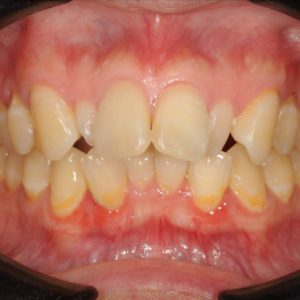

虫歯の治療、矯正の相談をご希望され来院されました。お口の中を診査(レントゲン写真、口腔内写真、視診)させていただいたところ、虫歯については問題なくきれいに歯磨きされているようでした。 正面から見るとジグザグしており、お口 […]

全体的な歯並びの矯正治療を行いました。治療期間は3年間。

ジグザグの歯並びを気にされてご来院されました。. 見た目の問題も大切ですが、それ以上に清掃がしにくいために虫歯・歯周病に非常になりやすく、不正咬合(良くないかみ合わせ)は顎の関節に負担をかけてしまい顎関節症を引き起こす可 […]

歯の大きさに対する顎の大きさのスペース不足により歯が並びきらず、ジグザグの歯並びおよび上の前歯が出っ歯になっていました。 左右4番の歯を抜歯することにより歯を並べるスペースを確保し、歯並びを揃えました。 全体の歯並びが綺 […]